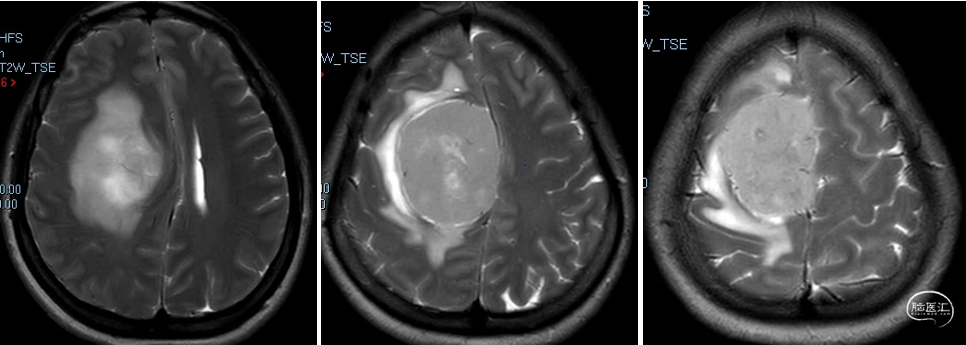

术前诊断:颅内多发脑膜瘤(右额顶部窦旁及右额部)。

术后影像